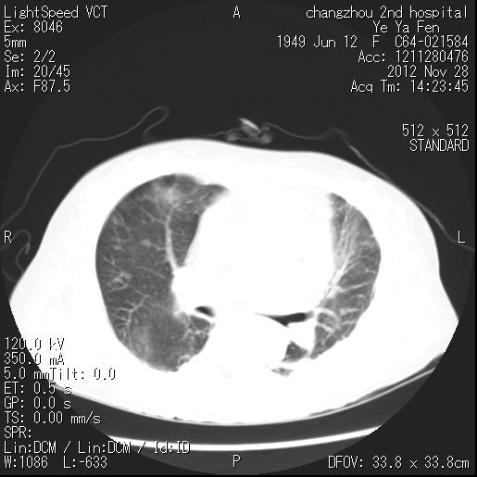

肺部CT检查